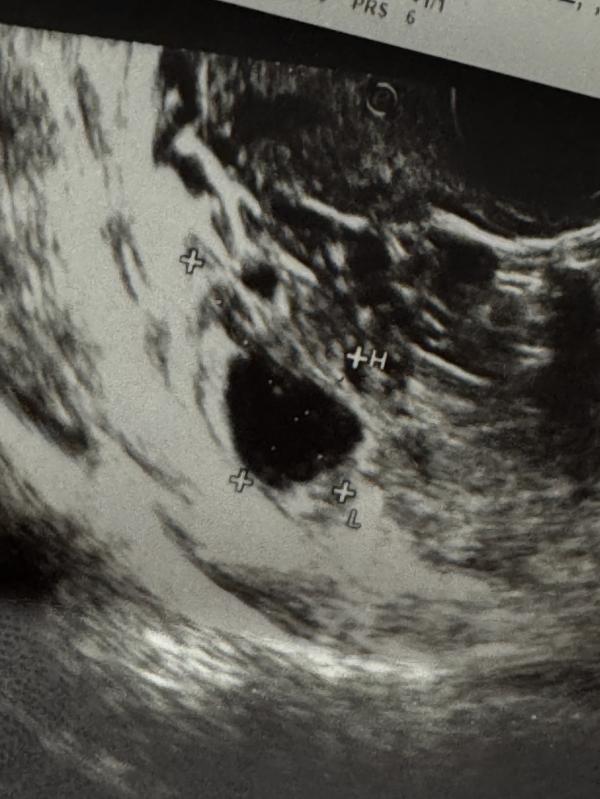

Хелп! Как вы думаете на фото фолликул несовулировавший или все таки желтое тело? 🧐

Сдайте прогестерон , будет точно ясно фолик это не лопнувший или желтое тело . А жидкость есть в позадиматочном , кровоток в нем какой ?

Жёлтое тело определяют по кровотоку в нём. Поэтому тут не понятно

Больше похоже на ЖТ, но надо кровоток смотреть.